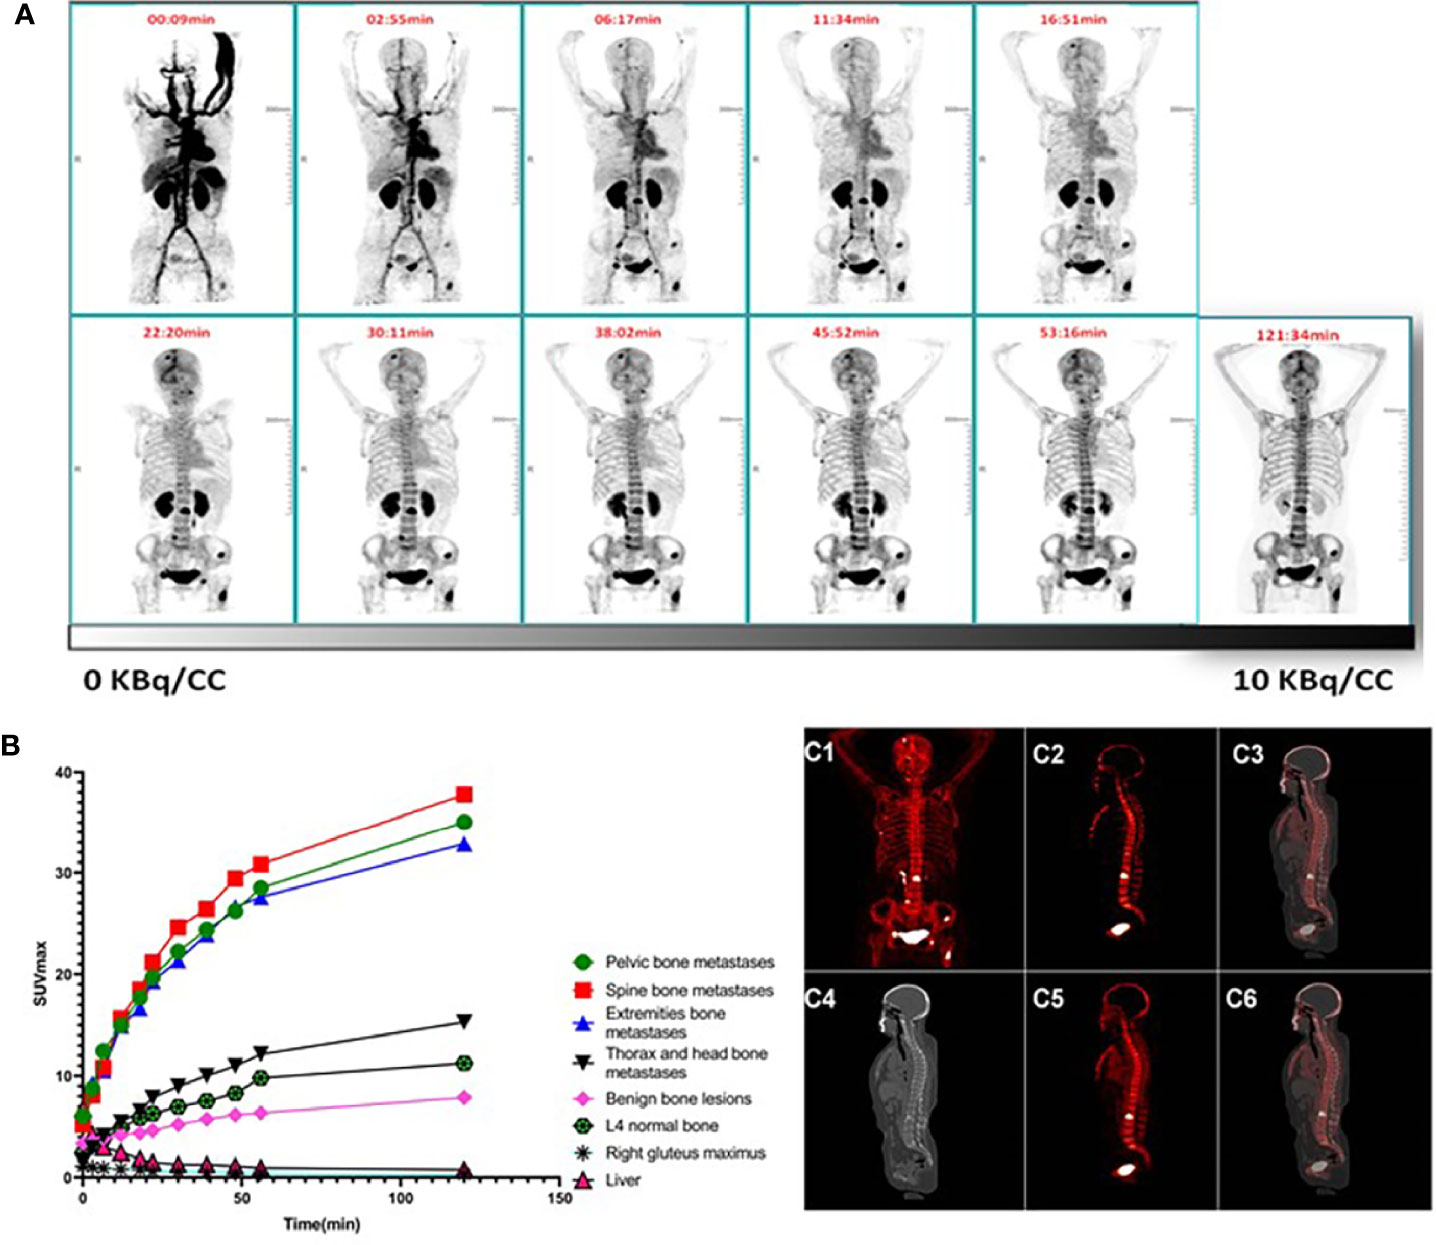

期間限定特別価格 Roentgen Signs 9780721663029 Abdomen: Imaging: Diagnostic in 医学一般の詳細情報

Roentgen Signs in Diagnostic Imaging: Abdomen: 9780721663029。PET Scans Guiding Chemo Boost Remission for Hodgkin Patients。Roentgen Signs in Diagnostic Imaging: The Chest。期間限定割引SW.13 特级黄小米 小米 あわ 粟 健康食糧 粗糧 40038y。 閉じる